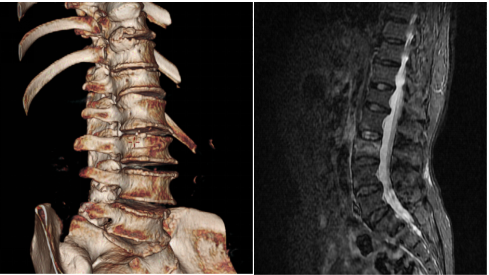

术前